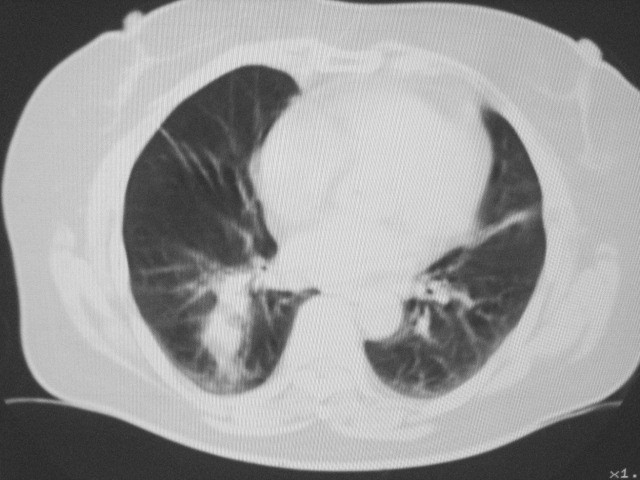

以下是引用清清楚楚在2007-8-28 7:13:00的发言:[br]右肺下叶可见斑片状高密度影,边缘模糊;右肺中叶内侧段及左肺舌段亦可见小斑片状模糊影。[br]考虑双肺感染,建议抗炎治疗后复查。

以下是引用天南地北在2007-8-27 23:49:00的发言:[br]右肺下叶可见斑片状高密度影,边缘模糊;右肺中叶内侧段及左肺舌段亦可见小斑片状模糊影。[br]考虑双肺感染,建议积极抗炎治疗后复查。

以下是引用天南地北在2007-8-27 23:49:00的发言:[br]右肺下叶可见斑片状高密度影,边缘模糊;右肺中叶内侧段及左肺舌段亦可见小斑片状模糊影。[br]考虑双肺感染,建议抗炎治疗后复查。

以下是引用难听在2007-8-28 13:17:00的发言:[br]右肺下叶背段支气管狭窄,是否可以考虑新生物伴阻塞性肺炎.请大家帮帮忙,这个病人是卫生局长的丈母娘.惹不起啊.